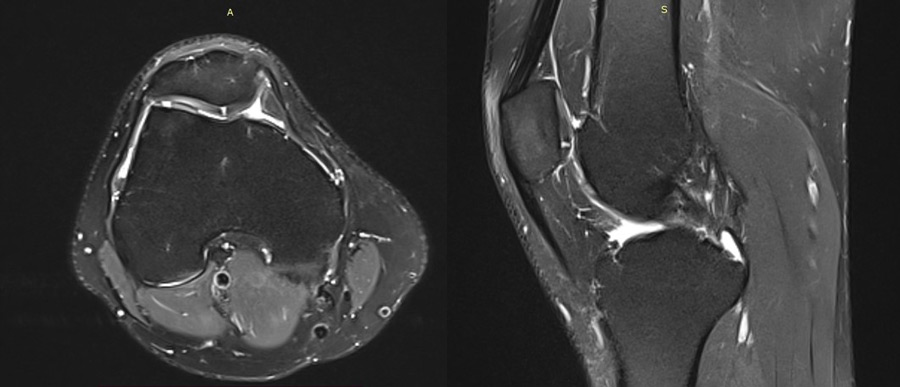

Management of chondral ‘kissing’ lesion of patella and trochlea: MRI 8 months post op

MRI 8 months post op

Clinical presentation 8 months post op

• No pain when standing, little pain when sitting for a long period of time (VAS 1/10)

• ext : 0°/ flex: 120° , Lachman +, Steinman negative med and lat, Varus and valgus stress test + in 30°, patellar grind test negative, J sign negative